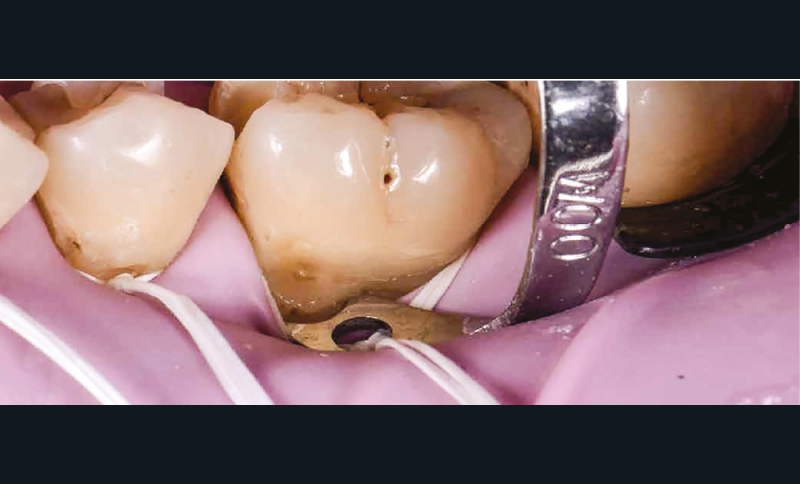

La première anesthésie se situe au niveau de la papille proximale entre 35 et 36. L’aiguille blanche de diamètre 0,30 mm et de longueur 16 mm est orientée de façon à avoir son repère légèrement décalé de la fenêtre du porte-aiguille (fig. 4). Ainsi, le biseau se pose à plat contre la muqueuse [1]. L’aiguille glisse doucement et de façon indolore dans la papille sur 2 mm et l’injection débute sans surpression sous contrôle électronique. Lorsque la papille montre une vasoconstriction suffisante, elle devient blanche et l’injection peut s’arrêter. La pièce à main s’oriente alors en direction de l’espace apical interdentaire avec un angle de 30 à 45° vestibulolingual (fig. 5). L’aiguille est mise en rotation pour pénétrer la corticale osseuse. Elle arrive ensuite dans la partie trabéculaire de l’os. Lorsque les deux tiers de l’aiguille sont sous la corticale, la rotation doit cesser et l’injection reprend avec une vitesse qui s’adapte électroniquement à la densité de l’os. Une demi-carpule d’articaïne 1/100 000 suffira à la restauration de ce secteur [2]. Le champ opératoire, le crampon, les ligatures sont placés (fig. 6) ; un crampon additionnel permet de descendre la ligature dans le sulcus de la 36 pour réaliser le soin vestibulaire (fig. 7). Les restaurations sont réalisées sans douleur (fig. 8) [3].